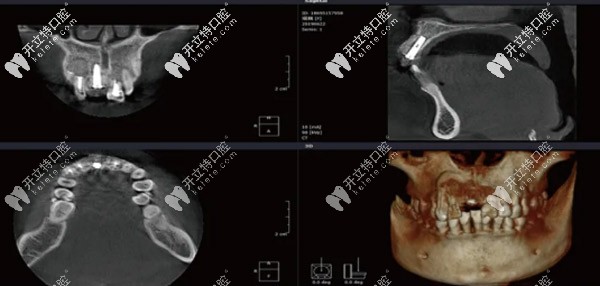

CBCT顯示11骨量高度18mm,近遠(yuǎn)中骨間隙10mm,唇舌側(cè)間隙6.3mm

在植體頂部和唇側(cè)植入Bio-Oss骨粉,壁鈦網(wǎng)加固13.12.21空腔內(nèi)植入Bio-Oss骨粉,覆蓋骨膜,嚴(yán)密縫合創(chuàng)口,手術(shù)當(dāng)日CBCT顯示種植體位置方向不錯(cuò),骨粉填充效果好,且13.12.21無松動(dòng)。

CBCT顯示種植位置方向良好,植骨區(qū)域成骨效果顯著。局部麻醉后,11牙槽頂和鄰牙齦緣切開后翻瓣,取出鈦網(wǎng),放入愈合基臺(tái),縫合。

基于顧客本身意愿,保留原牙不做美學(xué)修復(fù),種植牙顏色做與鄰牙相近的。12.13.21根尖切除后植入Bio-oss骨粉9個(gè)月后CBCT顯示成骨效果好,無松動(dòng)。